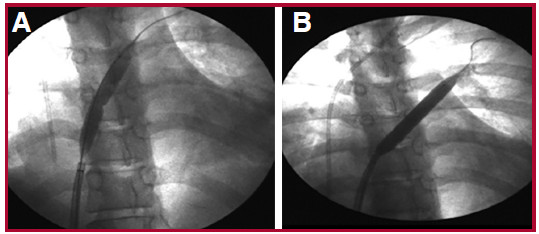

Se describe el caso de una paciente de sexo femenino de 20 años con diagnóstico previo de enfermedad mixta del tejido conectivo en 2018, sin seguimiento en los últimos 18 meses, tiroiditis de Hashimoto y bronquiectasias. Acudió a Guardia Externa por dolor abdominal, náuseas y diarrea. A su ingreso se constataron signos de insuficiencia cardíaca derecha (edemas en miembros inferiores, ingurgitación yugular sin colapso inspiratorio, reflujo hepatoyugular positivo y hepatomegalia), aumento de la intensidad del segundo ruido cardíaco a expensas del componente pulmonar, y soplo sistólico en foco tricuspídeo. El estudio diagnóstico inicial incluyó un electrocardiograma con signos de sobrecarga de cavidades derechas y bloqueo completo de rama derecha, y radiografía de tórax con aumento del segundo arco pulmonar derecho e índice cardiotorácico conservado. En el ecocardiograma Doppler se observó dilatación de cavidades derechas, disfunción grave del ventrículo derecho, insuficiencia tricuspídea grave con velocidad de regurgitación pico mayor que 4,5 metros por segundo (m/s), presión sistólica de la arteria pulmonar (PSAP) de 105 mm Hg, presión media de la arteria pulmonar (PAPm) de 55 mm Hg y derrame pericárdico leve. (Figura 1). Consecutivamente se realizó cateterismo cardíaco derecho que confirmó el diagnóstico de hipertensión arterial pulmonar (HAP) grave con presión media de aurícula derecha de 11 mm Hg, PAPm de 63 mm Hg, presión de enclavamiento pulmonar de 10 mm Hg, resistencia vascular pulmonar de 21 unidades Woods (UW), gradientes transpulmonar y diastólico de 53 mm Hg y 43 mm Hg respectivamente, gasto cardiaco (GC) de 3,20 L/min , índice cardíaco (IC) de 2,6 L/min/m2, índice de volumen sistólico (IVS) 23 ml/lat/m2, saturación venosa mixta de 65% y saturación arterial de 97%. Por falla ventricular derecha marcada, inició infusión endovenosa continua de furosemida sin respuesta favorable, soporte inotrópico con milrinona a dosis máxima que posteriormente se rotó a levosimendán 0.1 ug/kg/ min y soporte vasopresor con noradrenalina a dosis intermedias. La paciente evolucionó de forma desfavorable con signos de bajo gasto cardíaco y falla grave del ventrículo derecho. Debido a la falta de acceso inmediato a prostanoides parenterales, se realizó septostomía transeptal con balón de forma exitosa (fenestración de 5 mm) (Figura 2). La paciente presentó mejoría del estado clínico, con derivación precoz a un centro de mayor complejidad para valoración pretrasplante e inicio de infusión continua de epoprostenol endovenoso, con dosis en ascenso hasta 12 ng/kg/min, previo destete y suspensión de inotrópicos, e inicio de ambrisentán 10 mg y tadalafilo 10 mg con buena tolerancia. En el ecocardiograma Doppler control presentó dilatación moderada de cavidades derechas, PSAP de 70 mm Hg y solución de continuidad interauricular de 0,9 mm. (Figura 3) El cateterismo cardiaco evolutivo demostró descenso de la PAPm, RVP y mejoría del GC e IC (43 mm Hg, 7,3 UW, 4,8 l/min y 3,6 l/min/m2, respectivamente). Fue valorada por el servicio de Reumatología que confirmó el diagnóstico de lupus eritematoso sistémico por criterios clínicos e inmunológicos y nefritis lúpica grado II por biopsia renal.